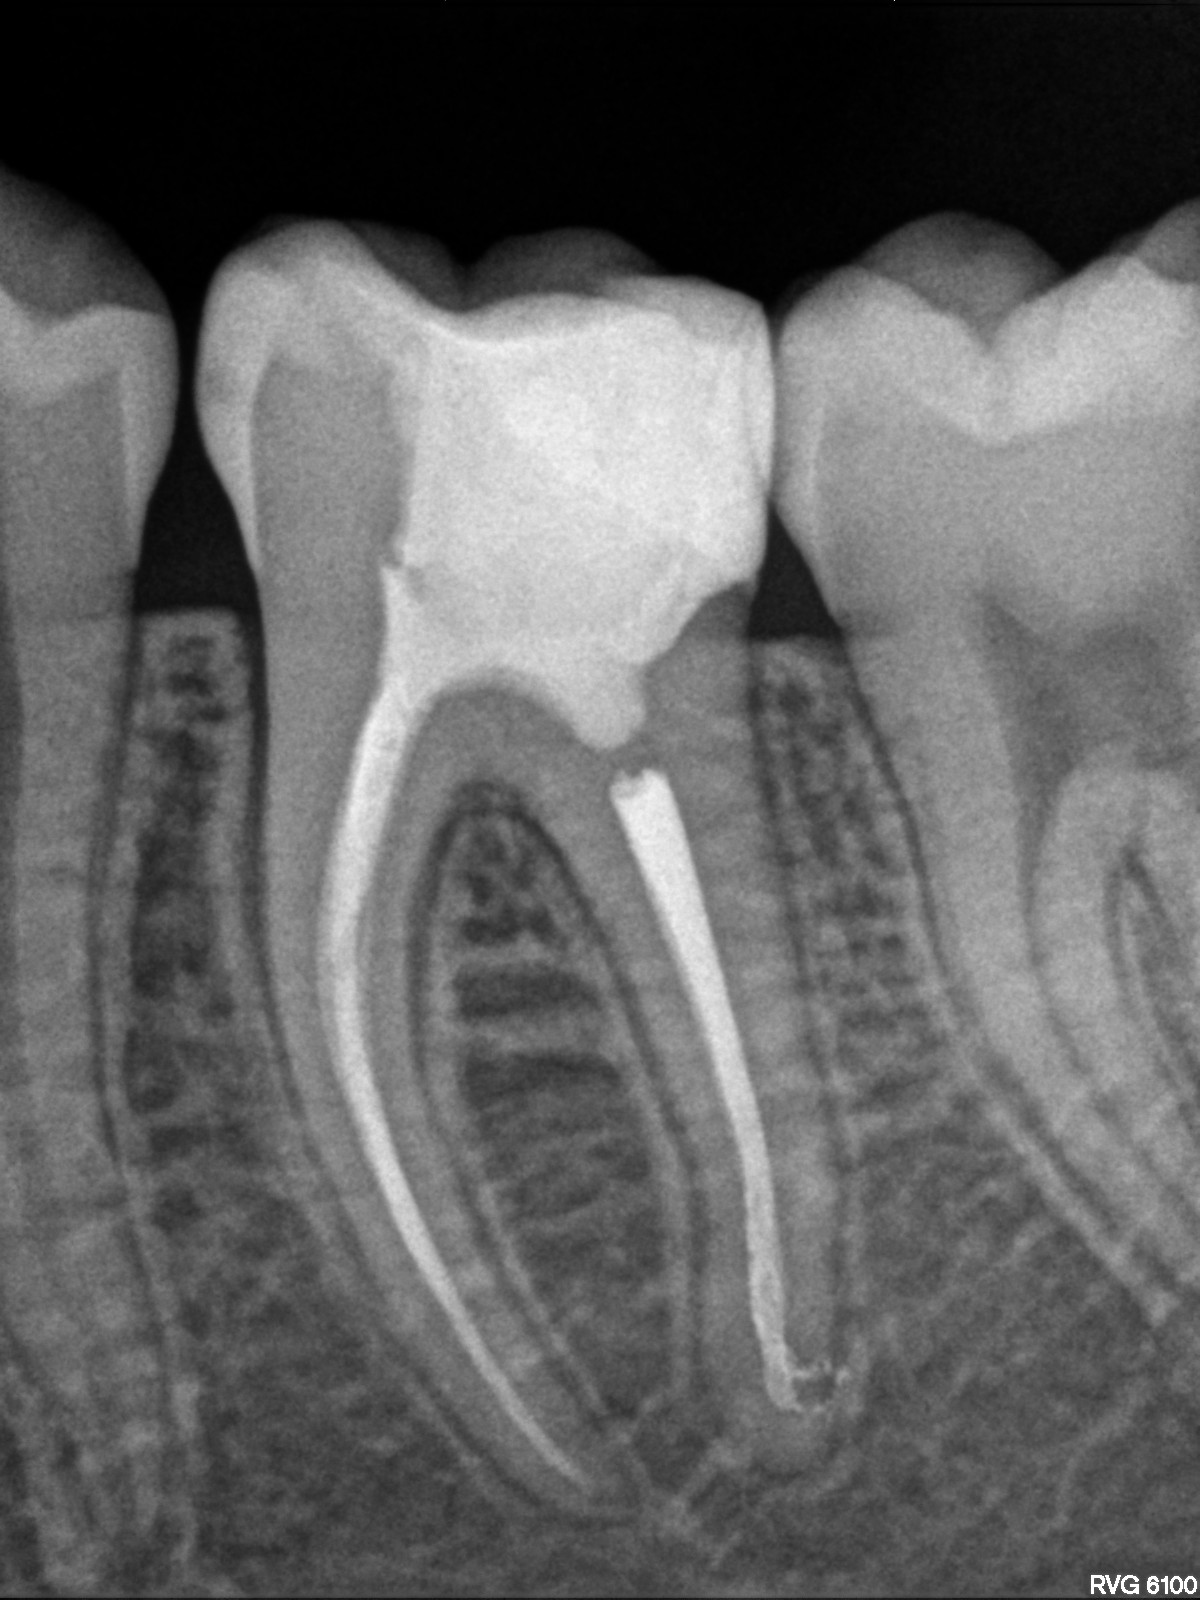

En los casos en los que una endodoncia previa no ha tenido el resultado esperado, es posible realizar una reendodoncia. Este procedimiento consiste en retirar el material de relleno anterior, localizar y tratar conductos que no fueron tratados inicialmente y aplicar un protocolo de desinfección riguroso antes de volver a sellar correctamente todo el sistema de conductos. La reendodoncia permite resolver infecciones persistentes y, en muchos casos, evitar la extracción, conservando el diente natural y mejorando su pronóstico a largo plazo.

Imágenes: Reendodoncia en un molar inferior derecho